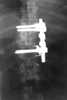

Congenital thoracolumbar vertebral wedging

Congenital vertebral anomalies are a collection of malformations of the spine. Most, around 85%, are not clinically significant, but they can cause compression of the spinal cord by deforming the vertebral canal or causing instability. [Source: Wikipedia ]